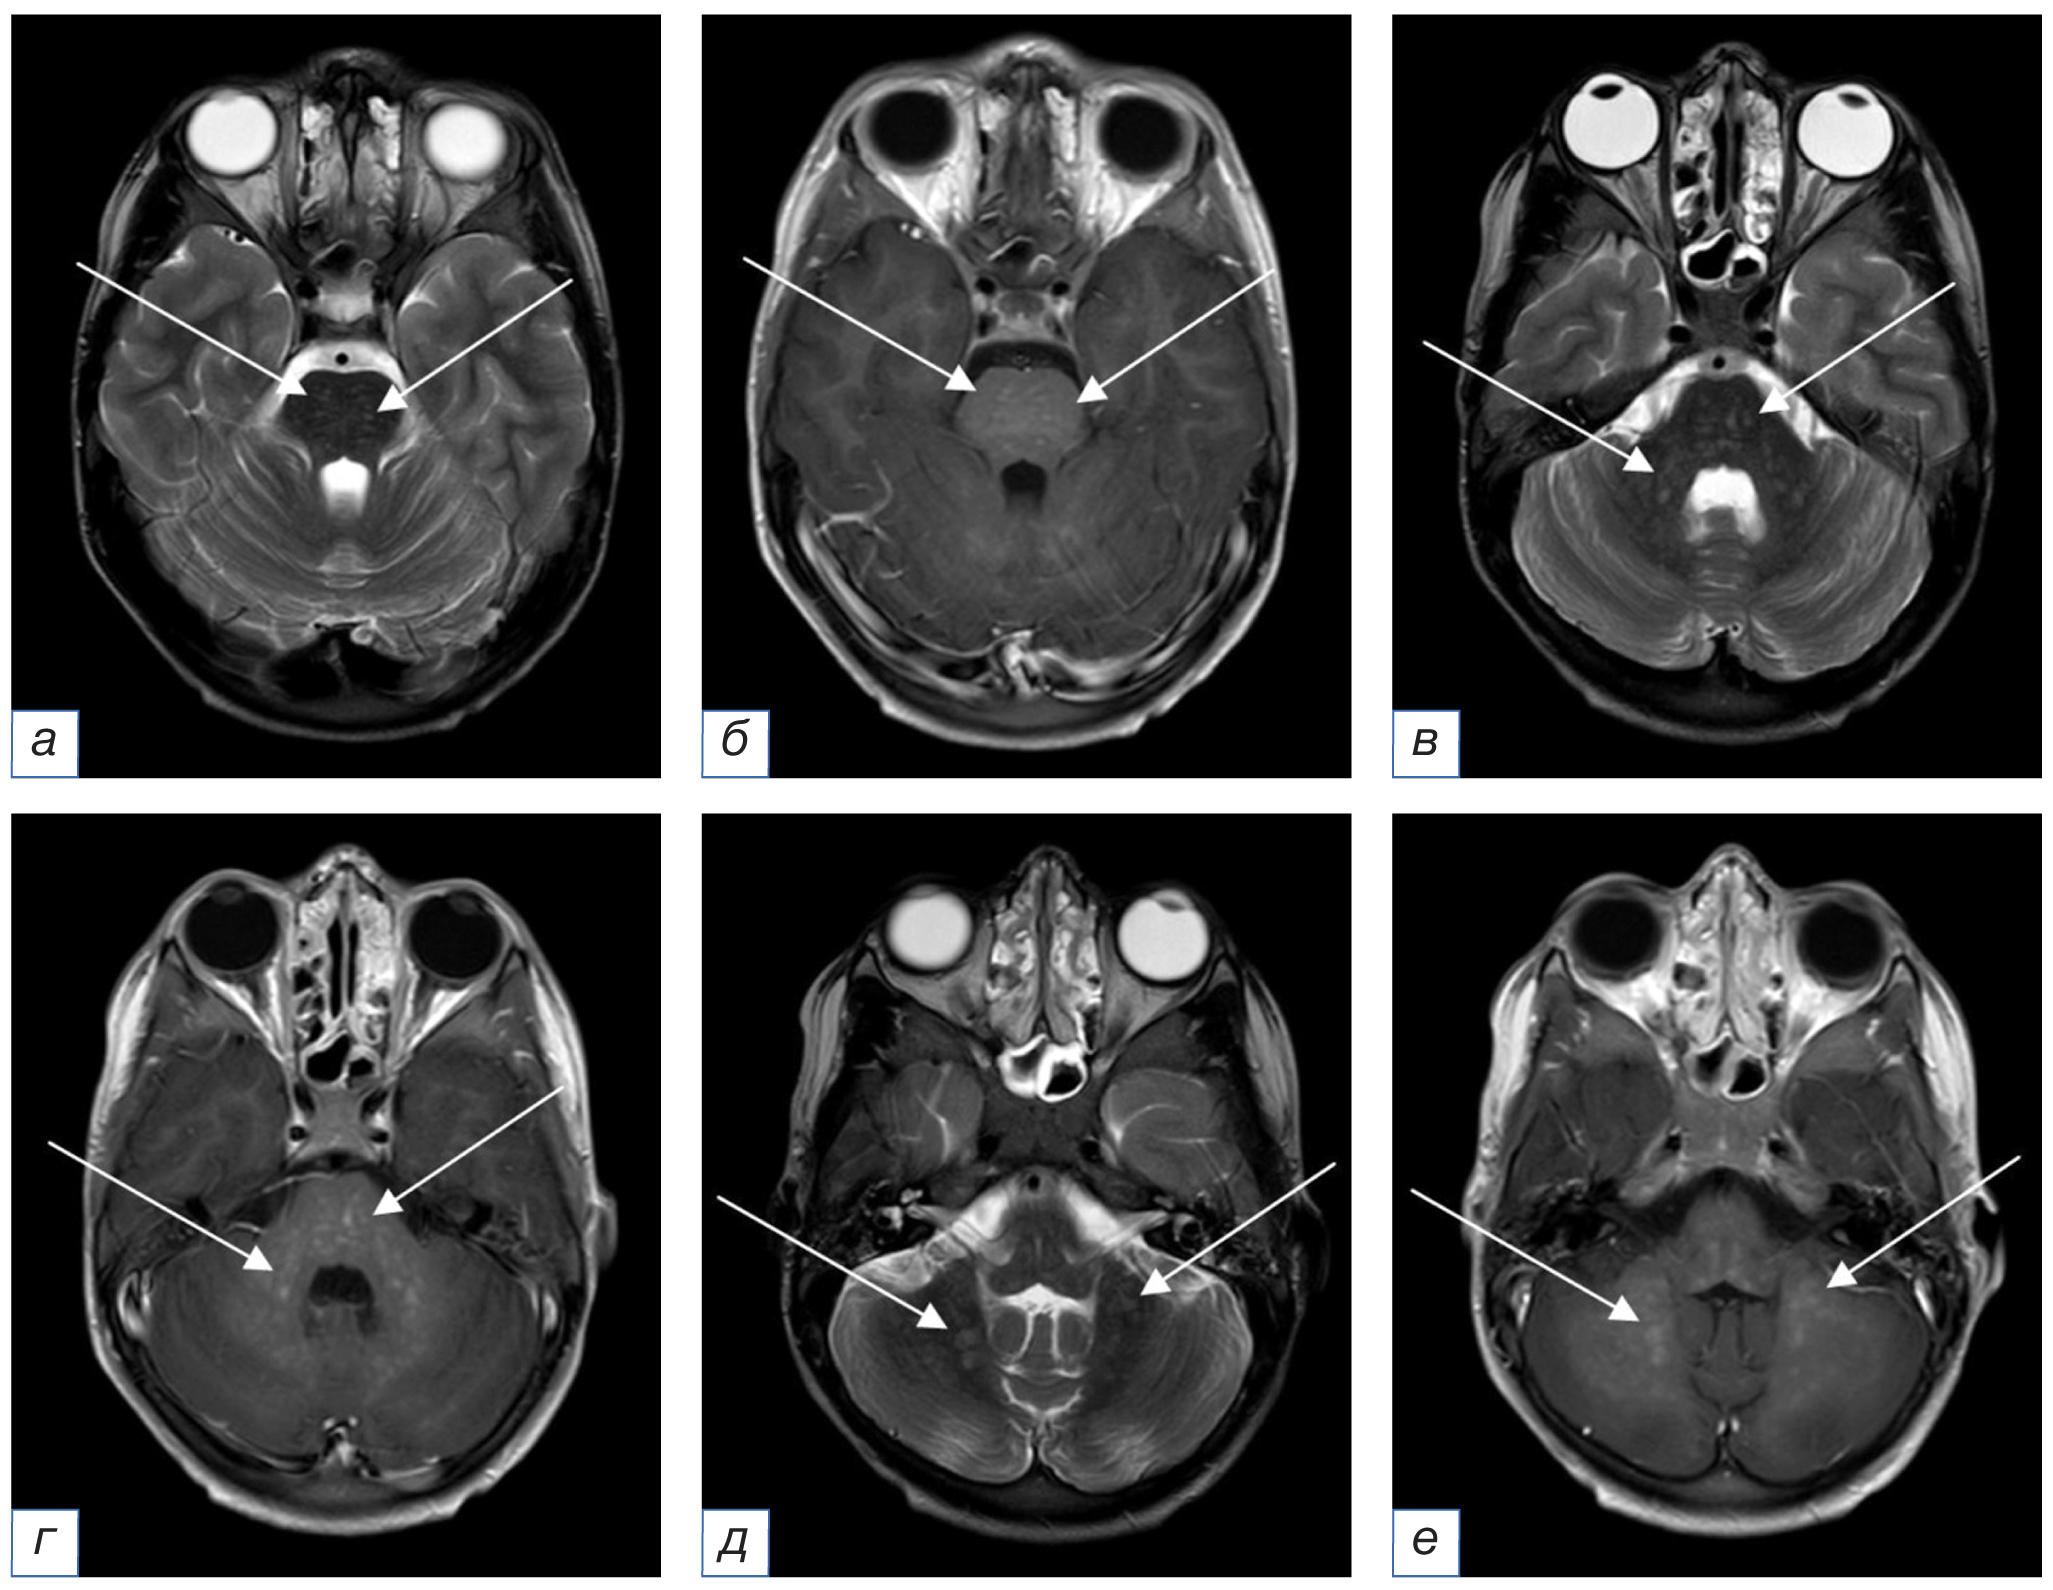

12.03.2020. При первичной МРТ (рис. 1) визуализированы множественные контрастпозитивные очаги, не ограничивающие диффузию, располагающиеся преимущественно субтенториально в мосту и распространяющиеся на мозжечковые ножки и белое вещество мозжечка. Выявляются единичные супратенториальные очаги, расположенные в базальных ганглиях. В качестве лечения проведен кратковременный курс пульс-терапии.

Рис. 1. Первичное МРТ головного мозга в аксиальной плоскости от 12.03.2020 без внутривенного контрастного усиления (a, в — режим Т2-ВИ; б, г — режим FLAIR): определяются множественные билатеральные точечные и криволинейные мелкие очаги измененного МР-сигнала, в том числе сливного характера, расположенные в мосту, мозжечковых ножках и белом веществе гемисфер мозга и мозжечка (стрелки). / Fig. 1. Primary MRI of the brain in the axial plane of March 12, 2020 without intravenous contrast enhancement (a, в — T2-weighted image; б, г — FLAIR): there are multiple bilateral punctate and curvilinear small foci of the altered MR signal, including confluent foci, located in the pons, cerebellar peduncles and the white matter of the brain hemispheres and cerebellum (arrows).